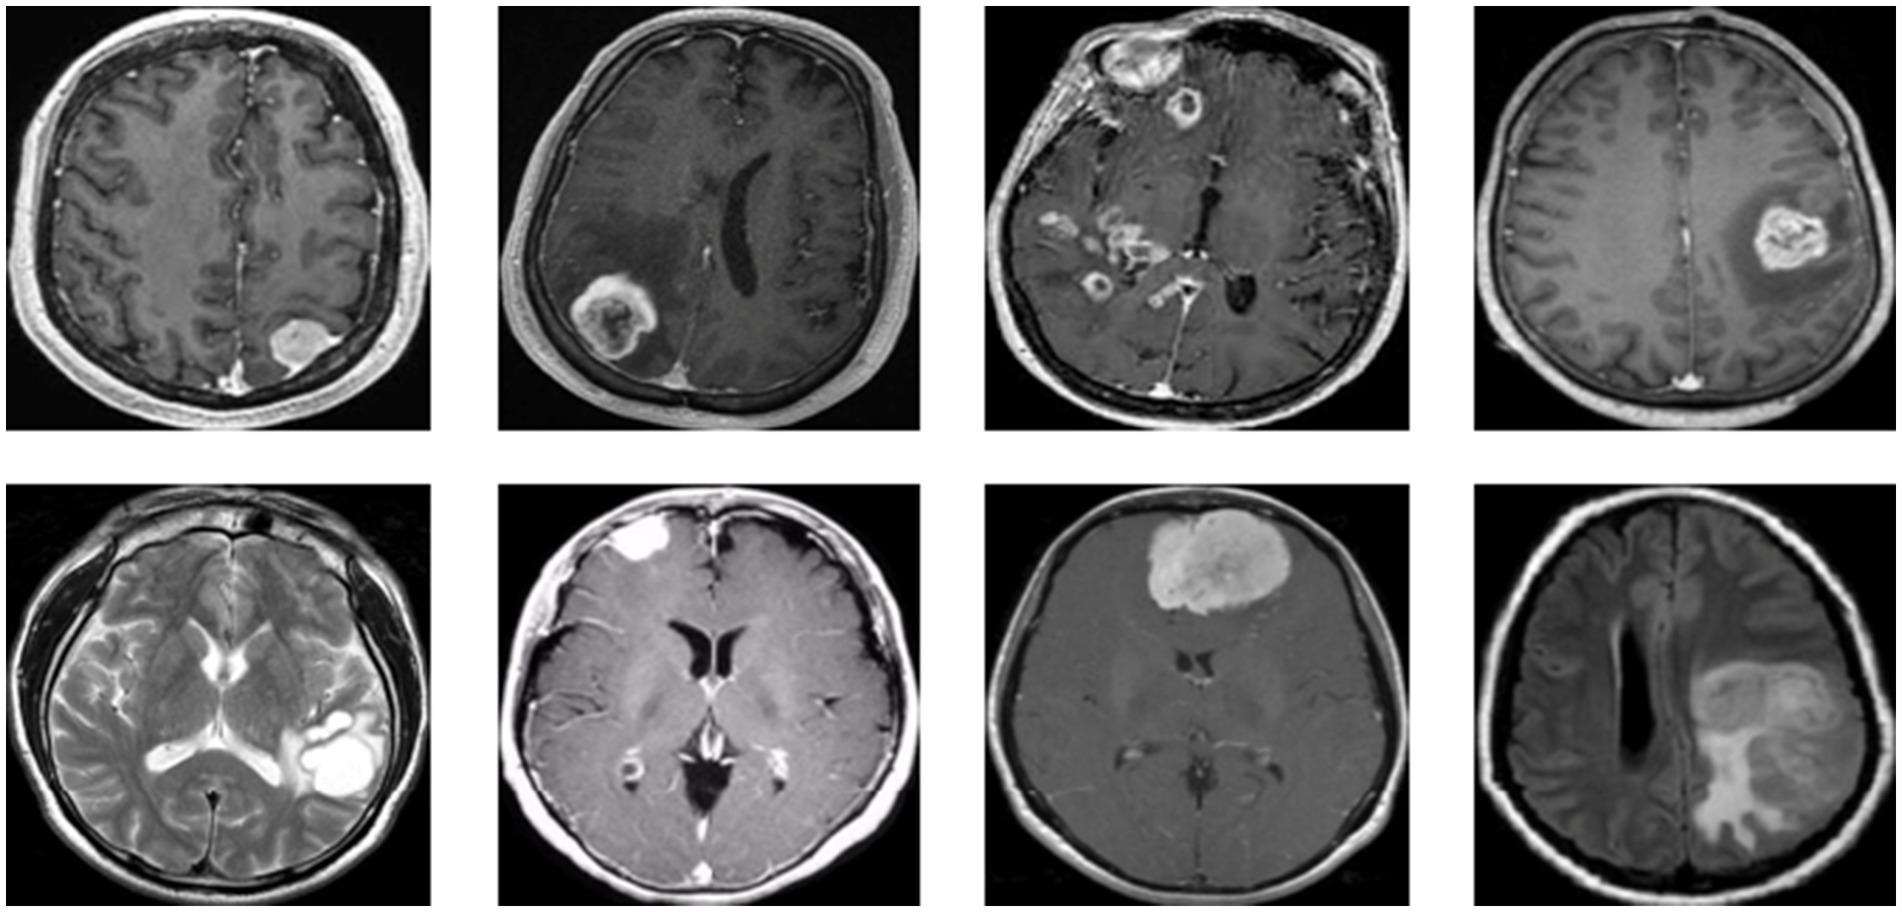

Figure 1 presents a representative MRI scan of a healthy brain, illustrating normal anatomical structures without any abnormal growths. In contrast, Figure 2 visualizes an MRI scan with a visible brain tumor, showing abnormal intensity regions that are indicative of pathological tissues. Figure 3 illustrates the distribution of MRI images across the defined classes, revealing an inherent imbalance in the dataset, which was addressed using augmentation techniques and loss function adjustments to ensure model robustness and generalizability.

Figure 2

Visualization for tumor MRI scan.